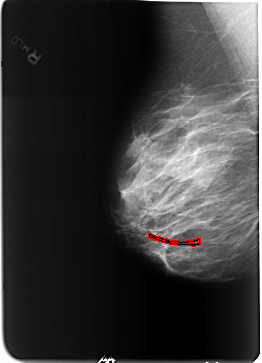

B_3212_1.RIGHT_MLO

FILE: B_3212_1.RIGHT_MLO.OVERLAY

TOTAL_ABNORMALITIES 1

ABNORMALITY 1

LESION_TYPE CALCIFICATION TYPE VASCULAR DISTRIBUTION N/A

ASSESSMENT 2

SUBTLETY 3

PATHOLOGY BENIGN_WITHOUT_CALLBACK

TOTAL_OUTLINES 1

BOUNDARY